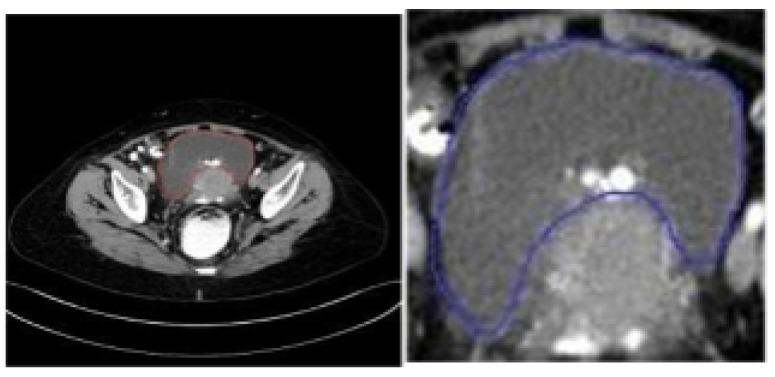

Deep learning architectures like ResNet and Inception have produced accurate predictions for classifying benign and malignant tumors in the healthcare domain. This enables healthcare institutions to make data-driven decisions and potentially enable early detection of malignancy by employing computer-vision-based deep learning algorithms. These CNN algorithms, in addition to requiring huge amounts of data, can identify higher- and lower-level features that are significant while classifying tumors into benign or malignant. However, the existing literature is limited in terms of the explainability of the resultant classification, and identifying the exact features that are of importance, which is essential in the decision-making process for healthcare practitioners. Thus, the motivation of this work is to implement a custom classifier on the ovarian tumor dataset, which exhibits high classification performance and subsequently interpret the classification results qualitatively, using various Explainable AI methods, to identify which pixels or regions of interest are given highest importance by the model for classification. The dataset comprises CT scanned images of ovarian tumors taken from to the axial, saggital and coronal planes. State-of-the-art architectures, including a modified ResNet50 derived from the standard pre-trained ResNet50, are implemented in the paper. When compared to the existing state-of-the-art techniques, the proposed modified ResNet50 exhibited a classification accuracy of 97.5 % on the test dataset without increasing the the complexity of the architecture. The results then were carried for interpretation using several explainable AI techniques. The results show that the shape and localized nature of the tumors play important roles for qualitatively determining the ability of the tumor to metastasize and thereafter to be classified as benign or malignant.

像ResNet和Inception这样的深度学习架构在医疗保健领域对良性和恶性肿瘤的分类中产生了准确的预测。这使医疗机构能够做出数据驱动的决策,并有可能通过采用基于计算机视觉的深度学习算法实现恶性肿瘤的早期检测。这些卷积神经网络(CNN)算法除了需要大量数据外,在将肿瘤分类为良性或恶性时,还能识别出重要的高层和低层特征。然而,现有文献在所得分类的可解释性方面有限,并且难以确定哪些确切特征是重要的,而这在医疗从业者的决策过程中至关重要。因此,这项工作的动机是在卵巢肿瘤数据集上实现一个定制分类器,该分类器具有高分类性能,随后使用各种可解释人工智能方法对分类结果进行定性解释,以确定模型在分类时赋予哪些像素或感兴趣区域最高的重要性。该数据集包括从轴向、矢状面和冠状面获取的卵巢肿瘤CT扫描图像。本文实现了包括从标准预训练的ResNet50派生而来的改进版ResNet50在内的先进架构。与现有先进技术相比,所提出的改进版ResNet50在测试数据集上表现出97.5%的分类准确率,且没有增加架构的复杂性。然后使用几种可解释人工智能技术对结果进行解释。结果表明,肿瘤的形状和局部特征在定性确定肿瘤转移能力从而将其分类为良性或恶性方面起着重要作用。